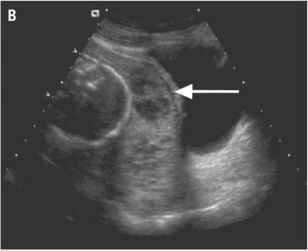

20+6w超声提示

完全性前置胎盘

测量部分指的是宫颈长度。

箭头指的是胎盘覆盖了子宫下段及宫颈内口。